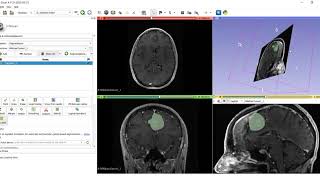

AI assisted segmentation using free tools 3D Slicer and Nvidia Clara video

AI-assisted segmentation using free tools - 3D Slicer and Nvidia Clara

AI-assisted segmentation using free tools - 3D Slicer and Nvidia Clara AI assisted segmentation tutorial using 3D SLICER

AI-assisted segmentation using free tools - 3D Slicer and Nvidia Clara

AI-assisted segmentation using free tools - 3D Slicer and Nvidia Clara AI assisted segmentation tutorial using 3D SLICER